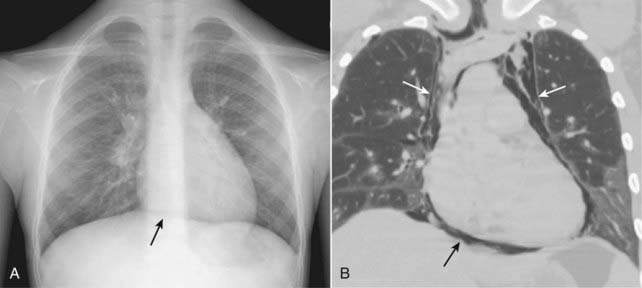

image

Figure 8-1 Visceral pleural line in a pneumothorax.

You must see the visceral pleural line to make the definitive diagnosis of a pneumothorax (solid white arrows). The visceral and parietal pleurae are normally not visible, both normally lying adjacent to the lateral chest wall. When air enters the pleural space, the visceral pleura retracts toward the hilum along with the collapsing lung and becomes visible as a very thin, white line with air outlining it on either side. Notice how the contour of the pneumothorax parallels the curvature of the adjacent chest wall.

Figure 8-2 Pneumothorax seen on CT.

As the lung collapses, it tends to maintain its usual shape so that the curve of the visceral pleural line (solid white arrows) parallels the curve of the chest wall (dotted white arrows). This is important in differentiating a pneumothorax from artifacts or other diseases that can mimic a pneumothorax. As it collapses, the lung on the side of the pneumothorax also tends to remain lucent until the lung loses almost all of its normal volume, at which point it appears opaque. This patient also has subcutaneous emphysema—air in the soft tissues—of the left lateral chest wall (white stars). The patient had suffered a stab wound.